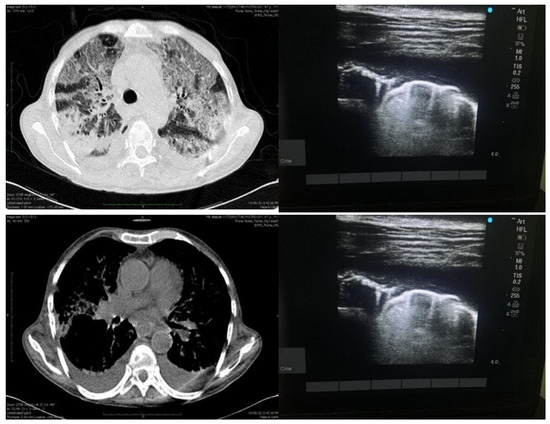

| LUS | CTSS | Total | Kappa | p-Value | ||

|---|---|---|---|---|---|---|

| Mild 0–11 | Moderate 12–18 | Severe >18 | ||||

| Mild | 59 | 07 | 02 | 68 | ||

| Moderate | 12 | 37 | 02 | 51 | 0.431 | <0.0001 |

| Severe | 06 | 24 | 03 | 33 | ||

| Total | 77 | 68 | 07 | 152 | ||

| Computed Tomography | Lung Ultrasonography |

|---|---|

| Sensitivity (95% CI) | 88% (78.44% to 94.36%) |

| Specificity (95% CI) | 76.62% (65.59% to 85.52%) |

| AUC (95% CI) | 0.82 (0.75 to 0.88) |

| Positive Predictive Value (95% CI) | 78.57% (68.26% to 86.78%) |

| Negative Predictive Value (95% CI) | 86.76% (76.36% to 93.77%) |

| Diagnostic accuracy | 82.24% |